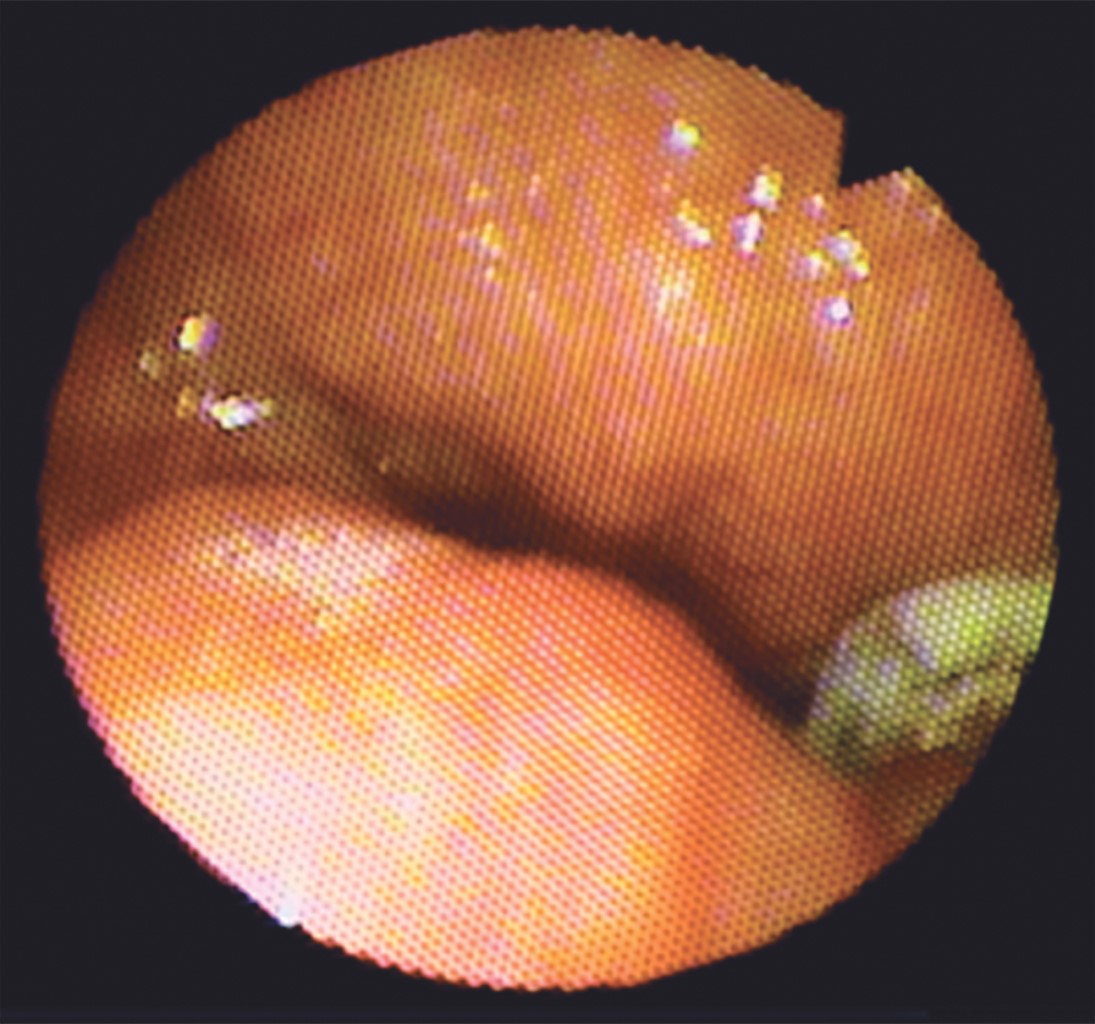

Los patrones de cierre velofaríngeo representan una descripción de una condición estática del esfínter en la fase terminal del cierre, por lo que el uso de nasofibroendoscopia es aceptado como el mejor método de análisis clínico para observar el esfínter velofaríngeo. Golding-Kushner y colaboradores,8 describieron a la nasofibroendoscopia como sistema de cuantificación y descripción de los movimientos de las estructuras del esfínter velofaríngeo, tal como se realizó en nuestro estudio obteniendo los ángulos e imágenes clínicas adecuadas para observar dicho esfínter (Figuras 5 y 6).

El patrón de cierre velofaríngeo dominante en la población mundial sin fisura palatina es el circular, los patrones de cierre velofaríngeo son categorizados de acuerdo a la pared que contribuye principalmente al cierre del esfínter velofaríngeo durante el habla. El cierre de la válvula velofaríngea es un mecanismo tridimensional que envuelve la función del velo y las paredes faríngeas, por lo que el patrón coronal ocurre cuando hay un movimiento excesivo del velo del paladar, que se desplaza a la pared faríngea posterior con menor movimiento de otras estructuras. El patrón sagital corresponde al movimiento de las paredes faríngeas laterales hacia la línea media con menor movimiento de la pared faríngea posterior y el velo del paladar. El patrón circular cuando todas las estructuras se desplazan juntas hacia la línea media y finalmente el patrón circular con rodete de Passavant, en el cual esta estructura que está formada por fibras del músculo constrictor superior de la faringe contribuye al cierre en la línea media (Figura 1).3,5,7,8,17,20